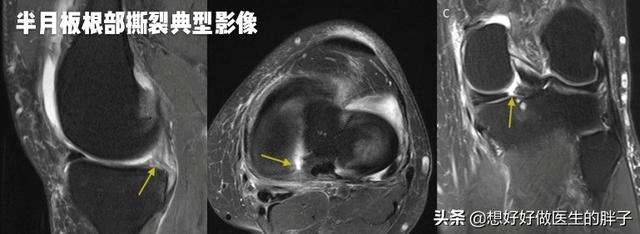

●如果是由于半月板损伤导致患者出现走路就疼,那么说明半月板可能发生了撕裂。下图就是典型的半月板发生撕裂的影像学资料,大家可以看到结构紊乱明显有一道裂缝的就是破裂的半月板。